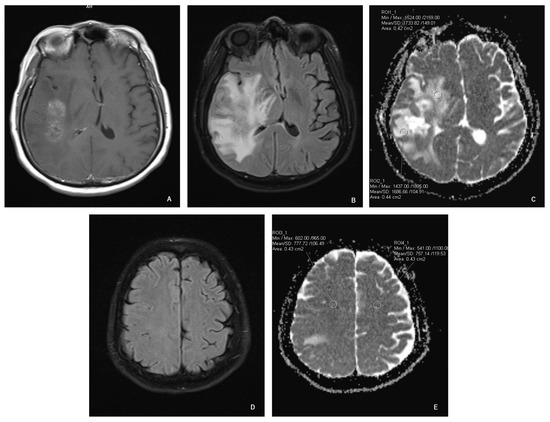

All scans were analyzed with the software provided by the scanner manufacturer (Syngo.via; Siemens; Munich, Germany). Each MRI study was evaluated by a radiologist. Using a freehand volume of interest tool we outlined the margins of the enhancing lesion. Two region of interest (ROI) circles were placed adjacent to the enhancing area in a random distribution (approximately 2 mm away from the enhancing margin, within the signal abnormality on FLAIR images), one ROI at least 4 cm away from the enhancement in the ipsilateral normal-appearing white matter (NAWM) and an additional ROI in the contralateral NAWM in a symmetric fashion (Figure 1). The surface area of ROI circles was 0.4–0.5 cm2 (Figure 1). The placement of ROIs was visually controlled between two time points to ensure consistency and to minimize potential variations. The visual control was implemented with the goal of placing the ROIs as identically as possible to the baseline MRI, to enhance the reliability and accuracy of our longitudinal assessments. The software calculated mean ADC values of the selected ROIs.

Figure 1. ROI placement. (A): T1 axial spin-echo showing the enhancing lesion; (B): axial FLAIR showing white matter hyperintensity adjacent to the enhancing lesion; (C): axial ADC map showing ROI placement adjacent to the enhancing lesion; (D): axial FLAIR showing normal-appearing white matter; (E): axial ADC at the same level as “D” showing ROI placement.